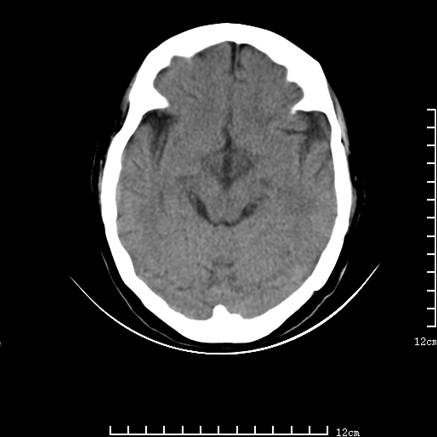

标题: V0514:女,72岁,偶有头晕,自诉记忆力减退,来诊。 [打印本页]

标题: V0514:女,72岁,偶有头晕,自诉记忆力减退,来诊。

1、考虑垂体腺瘤。

2、脑萎缩ct表现。

垂体腺瘤可能性大!另:轻度脑萎缩!

考虑垂体腺瘤可能性大。脑萎缩。